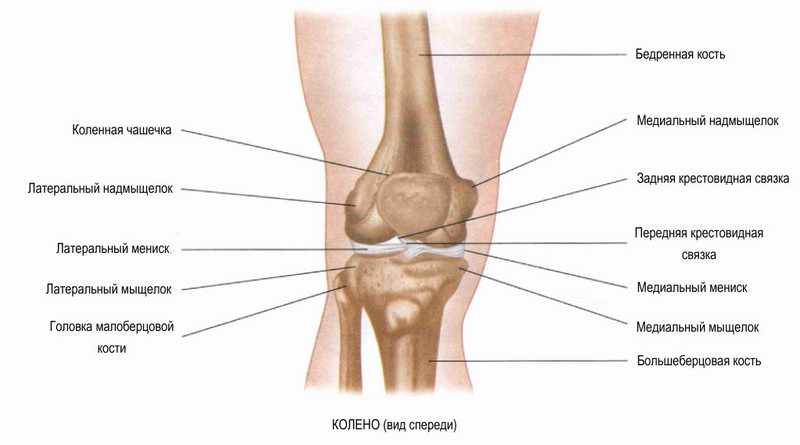

Перелом проксимального участка большеберцовой кости (область колена) включает любые виды нарушении целостности, локализованные выше бугристости, где расположены мыщелки. У бедренной кости их два – медиальный (внутренний) и латеральный (наружный).

Переломы могут быть полными и неполными. В первом случае наблюдается трещина, размозжение или ограниченное вдавление хряща. При полном переломе мыщелок (или его фрагмент) отходит полностью. Повреждение может быть сочетанным, когда происходит разрыв связок или повреждение мениска, а также травма межмыщелкового возвышения. Отдельно выделяются также компрессионный и импрессионный переломы.

Мыщелки — это округлые суставные поверхности, которые образуют нижнюю часть бедренной кости и входят в контакт с большеберцовой костью, создавая прочное сочленение.